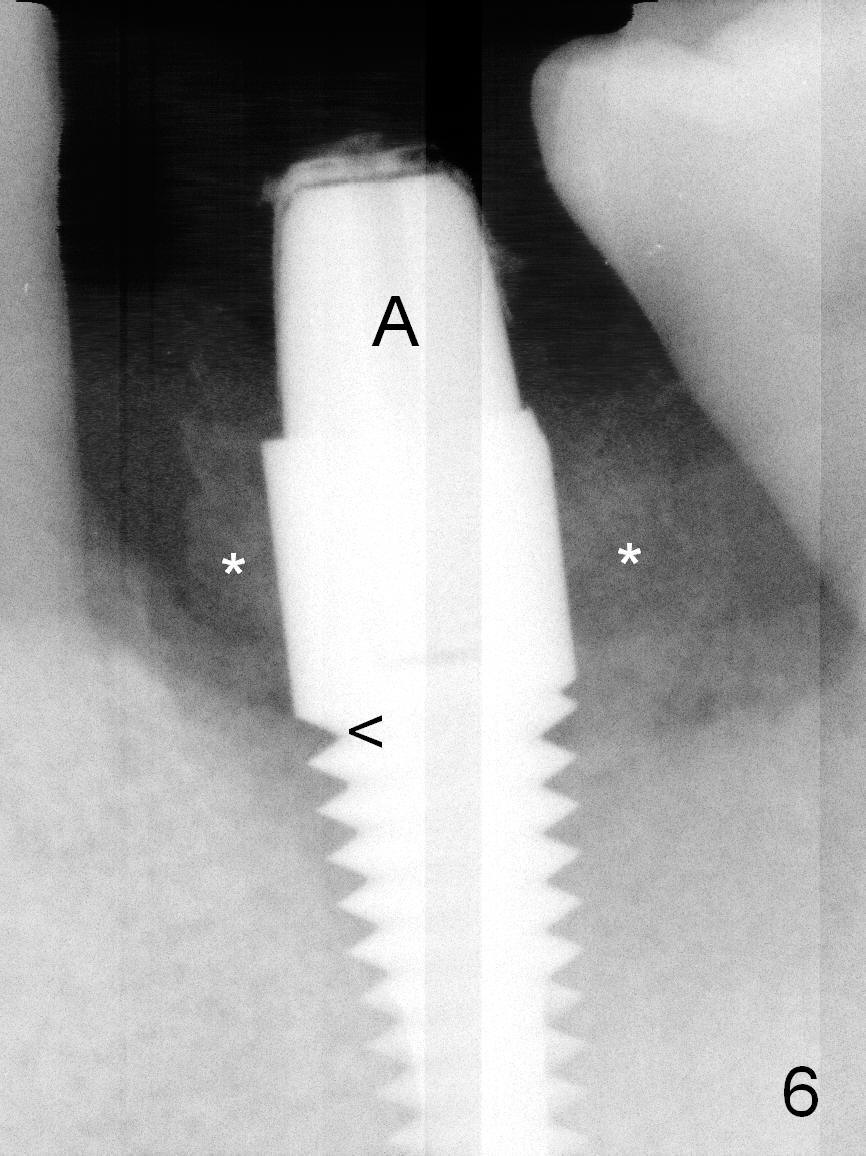

When the patient returns for #19 extraction and immediate implant, there is buccal (Fig.1 *) and lingual gingival swelling. The distobuccal root is exposed (D). Both the buccal and lingual walls are low. There is no septum. After removal of granulation tissue, an osteotomy is established in the bottom of the socket (slightly mesiolingually). The depth is approximately 3 mm in new bone (half of 6 mm and arrowhead). When the depth increases approximately 6 mm in new bone (Fig.3 arrowhead with 6x20 mm tap (T) in place), the Inferior Alveolar Canal is still invisible in PA. Panoramic X-ray has to be taken (Fig.4). So far infiltration anesthesia has been administered. When #2 sensor is inserted in the lingual vestibule, the patient feels pain and nausea. Lingual Nerve block is provided. The patient feels pain when further osteotomy is carried on. Since the depth of the osteotomy is confirmed by panoramic X-ray, Inferior Alveolar Nerve block is added. A 6x17 mm tissue-level implant is placed with clearance from the Inferior Alveolar Canal (Fig.5: red dashed line: the superior border of the Canal). Therefore, Lingual Nerve block allows lower placement of sensor so that the Inferior Alveolar Canal is detectable by PA.

The implant is placed lower by 1 thread (compare arrowheads in Fig.5,6). Bone graft (Fig.6 *) and Osteoplug are placed in the remaining socket (mainly mesiobuccodistally). An abutment (A) is placed for immediate provisional.